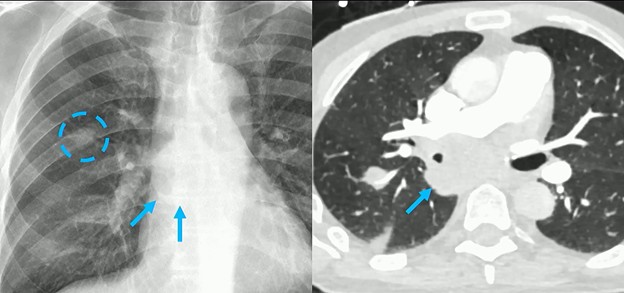

CT Correlation: Indeed, follow-up CT confirmed what the radiograph found:

- The presence of that right lung nodule.

- The massive subcarinal lymph node is clearly visible, showing exactly why the azygoesophageal interface was obscured.